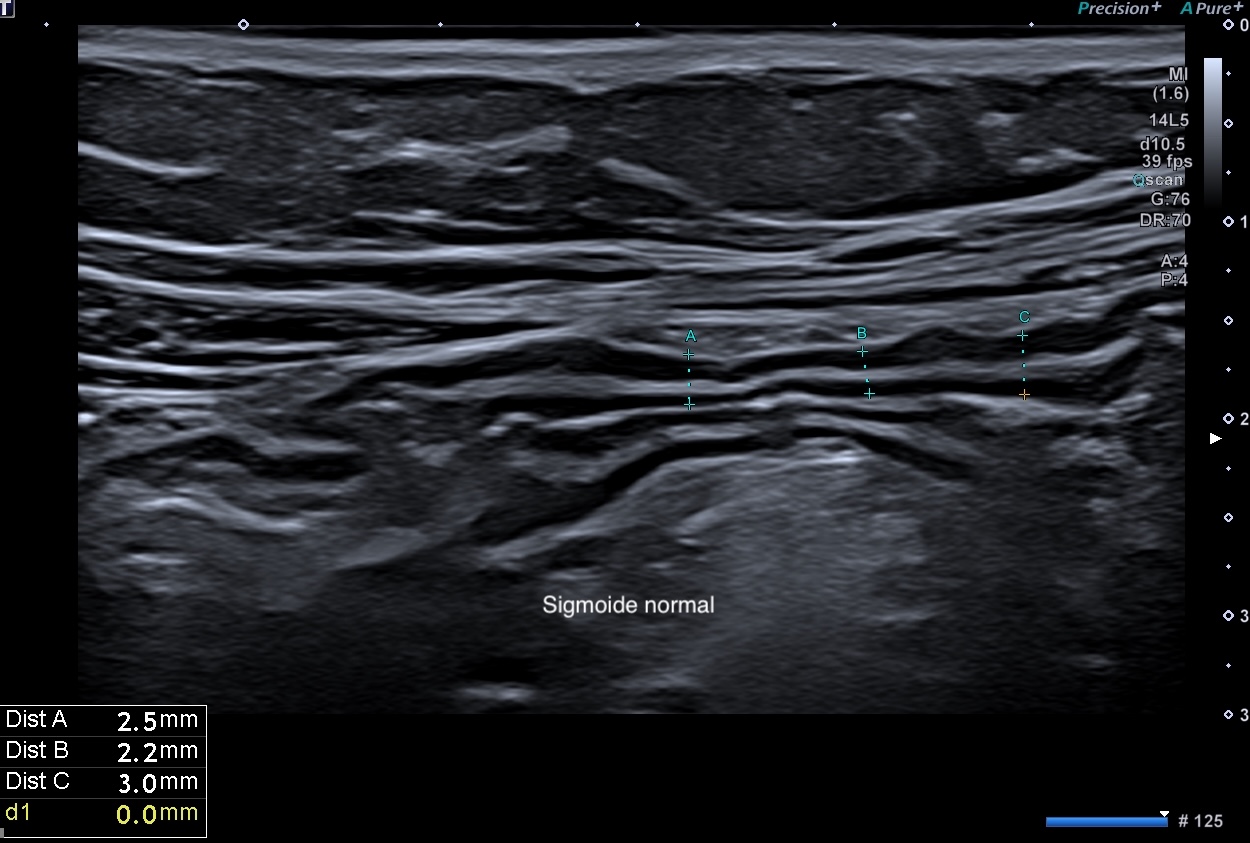

< 3 mm

Doppler = pas d'activité doppler

Graisse normale (pas d'infiltration)

Pas de ganglion (< 6 mm de petit axe)

Sigmoide paroi 2,5 mm